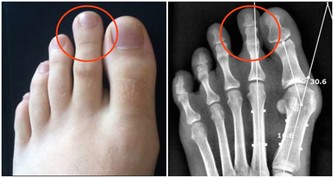

莧菜平衡酸鹼值,補血又使痛風消。莧菜有紅莧、白莧,應該大量推廣。

尿酸痛風的人,可以每天吃一碗莧菜湯,或像我們客家人用莧菜煮麵線,但是不要放吻仔魚。

莧菜能平衡酸鹼,你的尿酸痛風就會好。

莧菜補血,就是紅莧菜,又使痛風消,

所以每天用一碗面線、一把莧菜,保證不會體重增加,保證尿酸痛風全部消掉。